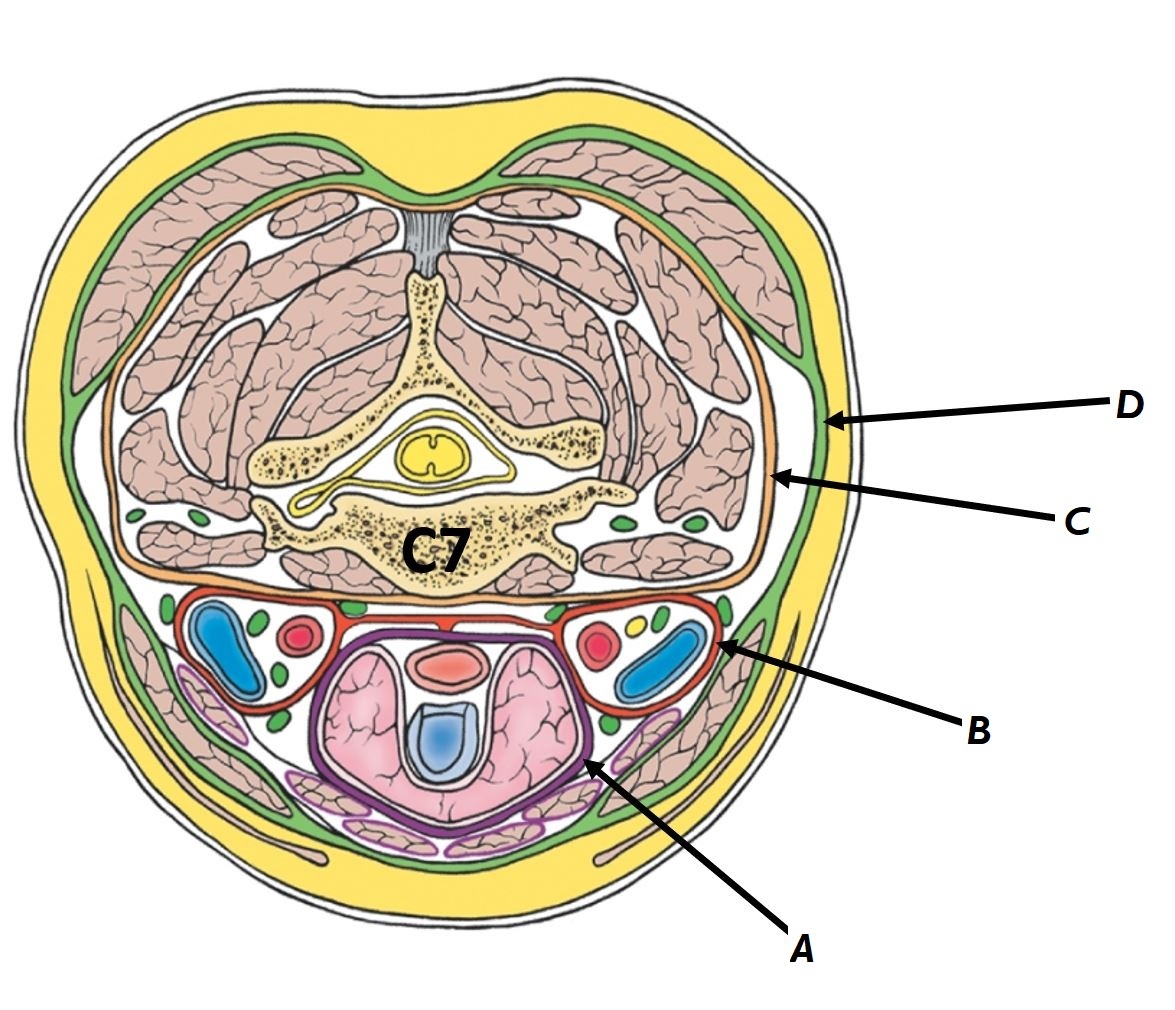

Name structures A to D

A - Pretracheal fascia

B - Carotid sheath

C - Prevertebral fascia

D - Investing fascia